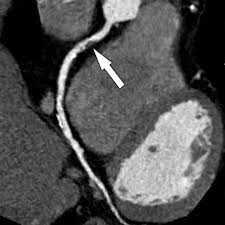

Как выглядит атеросклероз на КТ? Ангиография выявляет сужение правой внутренней сонной артерии атеросклеротической бляшкой. Исследование также позволяет наиболее точно изменить степень сужения сосуда (процент стеноза по методикам ESCT или NASCET). Ангиографию обязательно делать людям с выявленной патологией сосудов на УЗДГ, а также пациентам с повторяющимися инсультами.